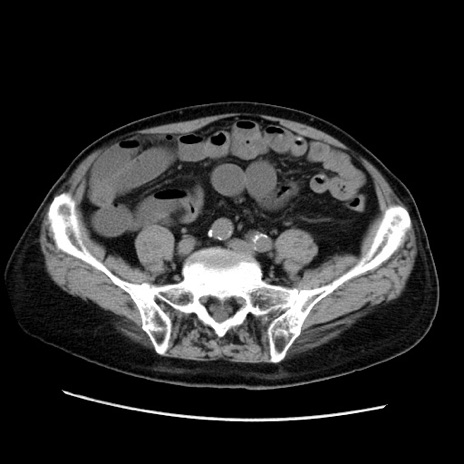

症例21(横断像)

【症例】70歳代男性

【現病歴】肝硬変・肝細胞癌にてかかりつけの方。約9時間前に食後より腹痛出現。症状が徐々に増悪し、嘔吐出現したため来院。

【既往歴】肝硬変、肝細胞癌(RFA、TACE後)